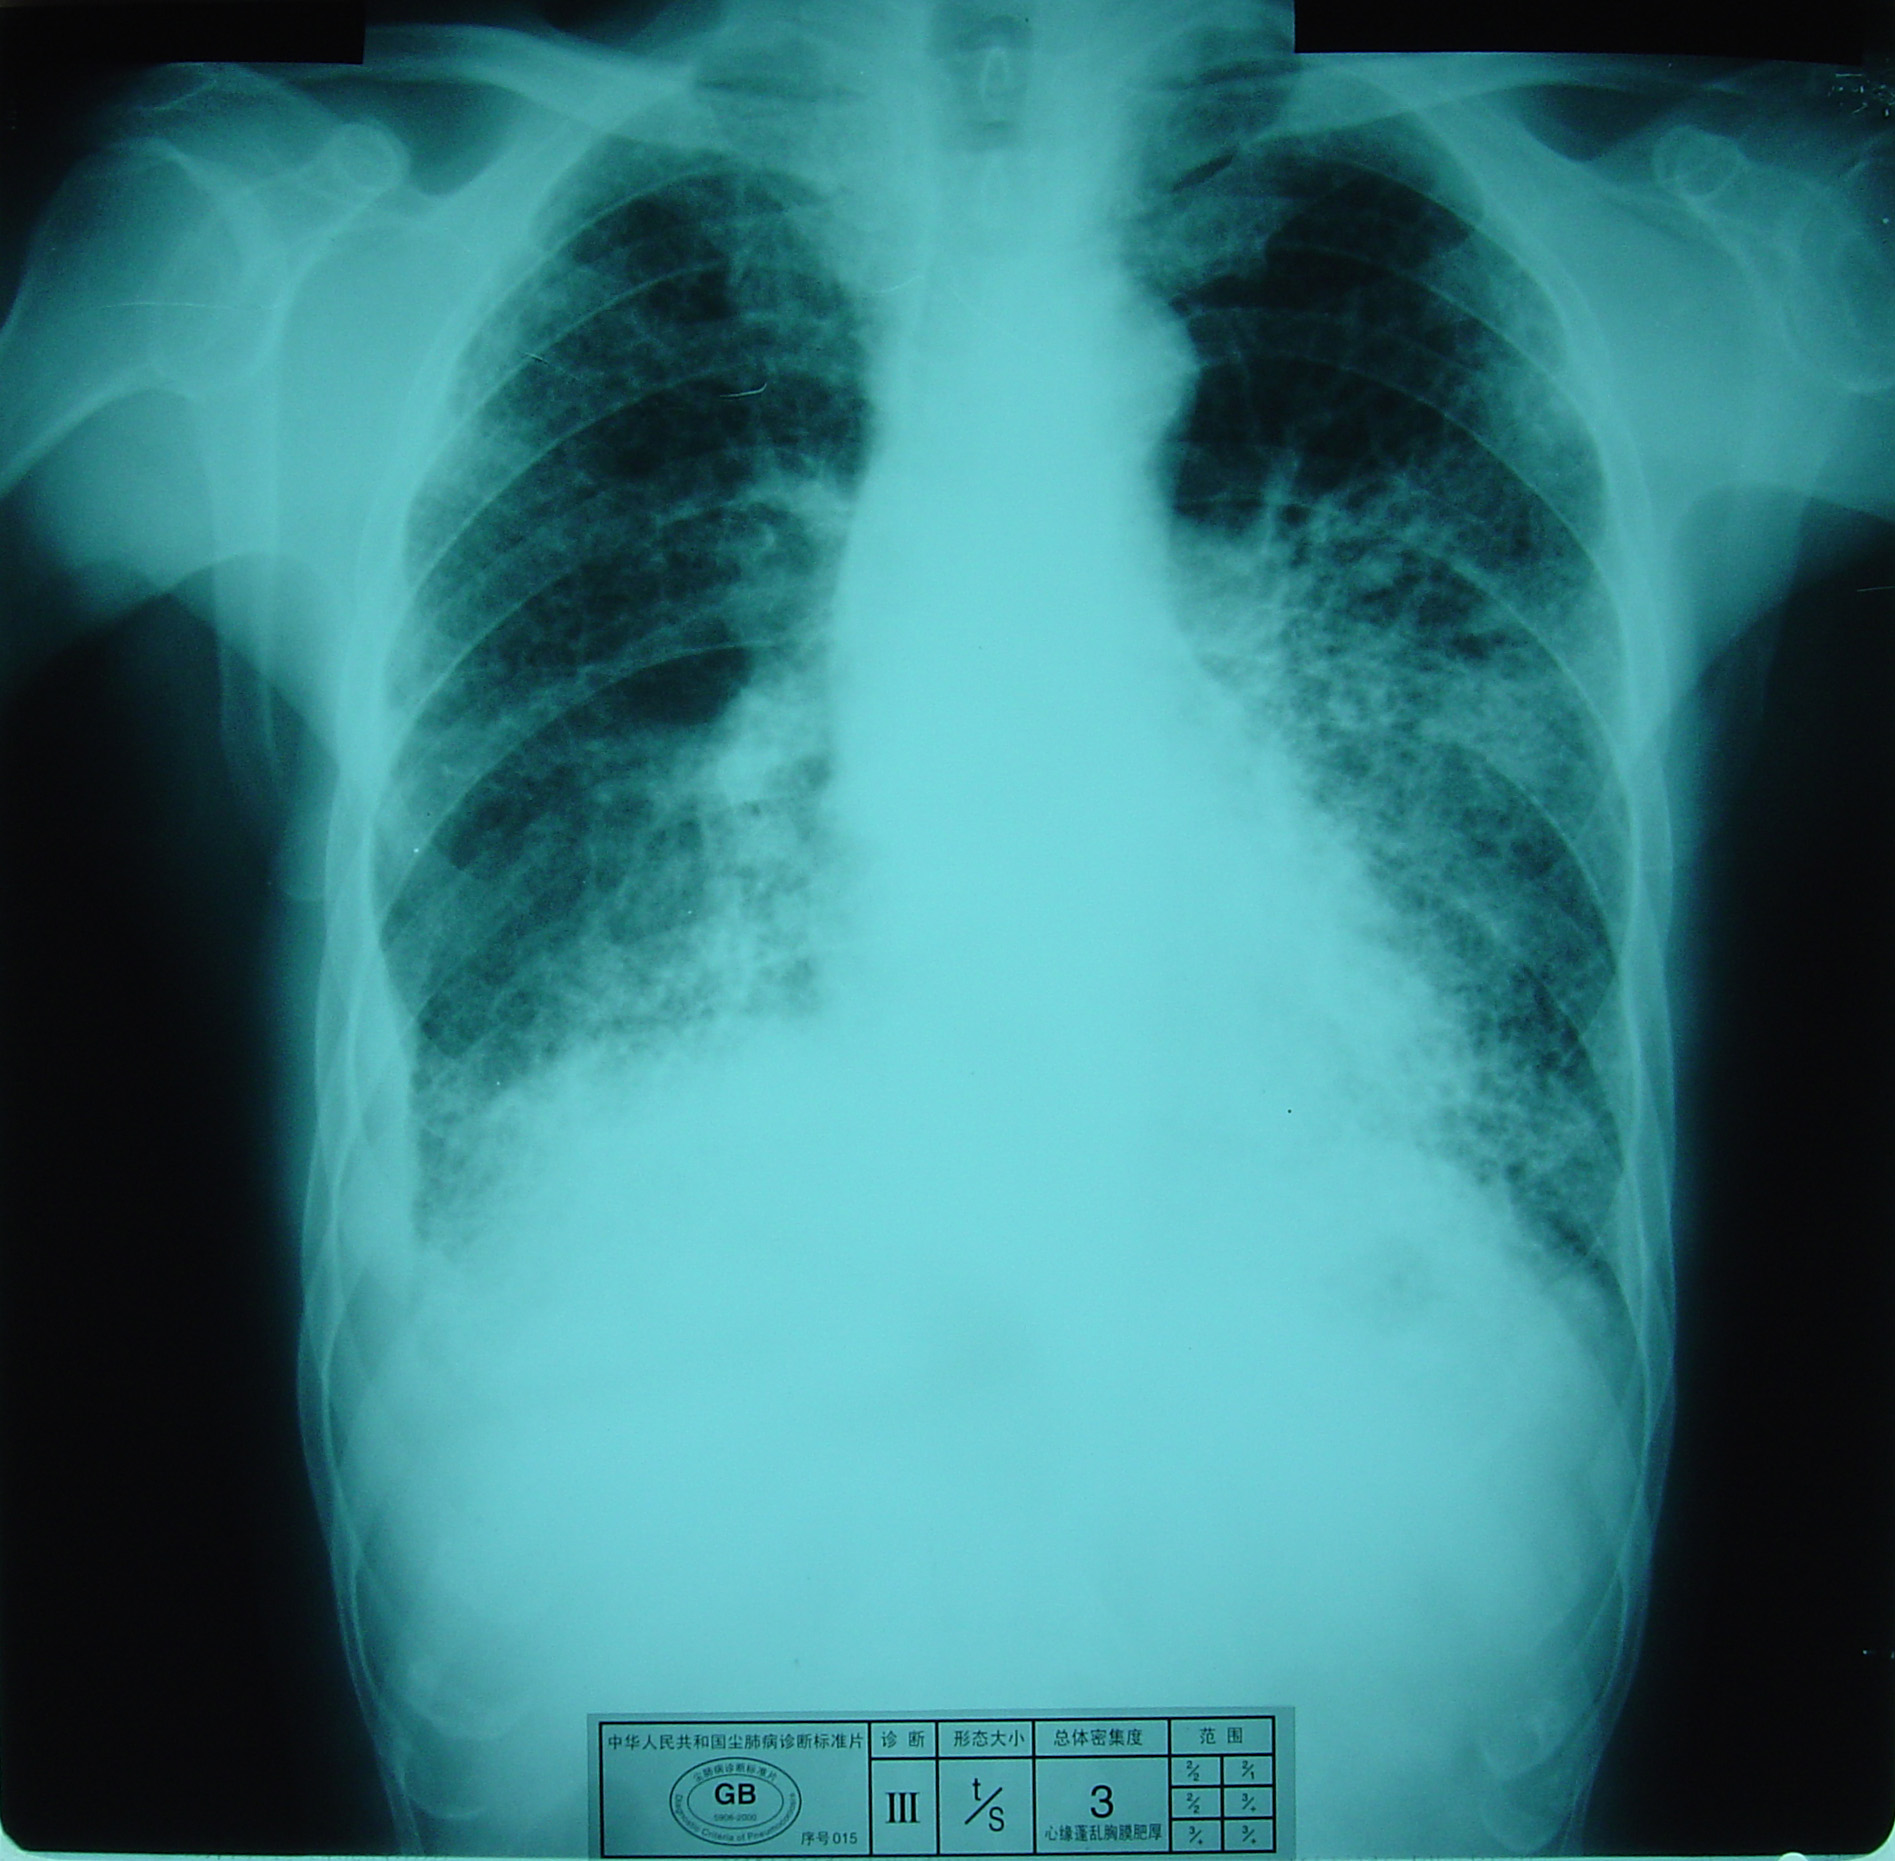

(2)X射线胸片表现:矽肺X射线胸片影像是肺组织矽肺病理形态在X射线胸片的反映,是“形”和“影”的关系,与肺内粉尘蓄积、肺组织纤维化的病变程度有一定相关关系,但由于多种原因的影响,并非完全一致。这种X射线胸片改变表现为X射线通过病变组织和正常组织对X射线吸收率的变化,呈现发“白”的圆形或不规则形小阴影,作为矽肺诊断依据。X射线胸片上其他影像,如肺门变化、肺气肿、肺纹理和胸膜变化,对矽肺诊断也有参考价值。在X射线胸片上,肺野内直径或宽度不超过10mm的阴影。小阴影按其形成分为圆形和不规则形两类。

2)不规则形小阴影:多为接触游离二氧化硅含量较低的粉尘所致,病理基础主要是肺间质纤维化。表现为粗细、长短、形态不一的致密阴影。阴影之间可互不相连,或杂乱无章的交织在一起,呈网状或蜂窝状;致密度多持久不变或缓慢增高。按其宽度可分为s(<1.5mm)、t(1.5~3.0mm)、u(3.0~10mm)三种类型。早期也多见于两肺中下区,弥漫分布,随病情进展而逐渐波及肺上区。

不规则形小阴影(u类小阴影)

3)大阴影:在X射线胸片上,肺野内直径或宽度超过10mm的阴影,为晚期矽肺的重要X射线表现,形状有长条形、圆形、椭圆形、或不规则形,病理基础是团块状纤维化。大阴影的发展可由圆形小阴影增多、聚集,或不规则小阴影增粗、靠拢、重叠形成;多在两肺上区出现,逐渐融合成边缘较清楚、密度均匀一致的大阴影,常对称,形态多样,呈八字形等,也有先在一侧出现;大阴影周围一般有肺气肿带的X射线表现。

大阴影

3)尘肺叁期:有下列表现之一者:

a) 有大阴影出现,其长径不小于20mm,短径不小于10mm;

b)有总体密集度为3级的小阴影,分布范围超过4个肺区并有小阴影聚集;

c) 有总体密集度为3级的小阴影,分布范围超过4个肺区并有大阴影。

尘肺叁期

尘肺叁期

尘肺叁期